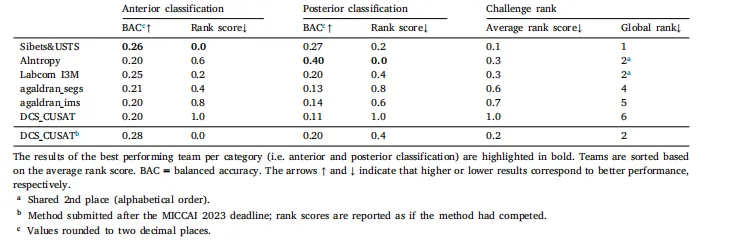

Table 2Results and ranking of proposed solutions by each team for Task 1 (classification of the anterior and posterior CoW variant) on the test set

表2 各团队针对任务1(Willis环前部和后部变异型分类)在测试集上提出的解决方案的结果及排名